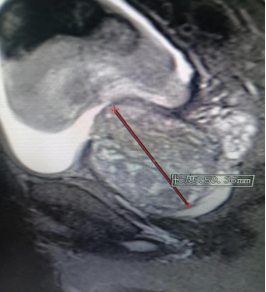

每当夜深人静的时候 您是否有尿频、尿急、夜尿多 总是在如厕或正在如厕的路上 “男”言之隐 痛苦不堪 …… 近日,94岁高龄的刘老爷子在孙子的陪同下来到贵州航天医院泌尿外科,因为排尿困难10余年,存在尿等待、尿无力、尿线细弱、尿不尽等问题,夜尿约7-8次,1月前出现无法排尿,反复留置导尿管,痛苦不堪。 因患者72岁儿子患有前列腺增生症,不久前在我院泌尿外科进行了前列腺钬激光剜除手术,对治疗效果较为满意,术后3天拔除尿管正常排尿出院,所以家人就抱着试一试的态度来到航天医院泌尿外科咨询。 泌尿外科根据患者病情及辅助检查,结合尿动力学检查排除神经源性膀胱,诊断为:前列腺增生症。 术前磁共振提示前列腺重度增生 泌尿外科团队为该患者制定了“经尿道前列腺钬激光剜除术”治疗方案。手术过程顺利。 经尿道前列腺钬激光剜除术手术中 激光剜除前列腺 粉碎前列腺组织 术后3天拔除导尿管,拔管后患者排尿较为顺畅,解决了困扰刘老爷子十余年的“男”题,极大提高了生活质量! 术前 术后 前列腺钬激光剜除术 (HoLEP)及前列腺增生科普 什么是前列腺增生 良性前列腺增生,也称为前列腺肥大症,是一种男性常见的疾病,其主要表现为前列腺组织的异常增生。这种增生主要发生在前列腺的尿道周围,使得尿道变窄,从而引起一系列的问题。大约50%的50岁以上的男性都会出现前列腺增生的症状。在大多数情况下,前列腺增生是一个自然的衰老过程,不会对健康构成威胁。但是,如果增生的前列腺组织阻塞了尿道,可能会引发一系列的问题。 前列腺增生症状 *尿频:尤其是夜间尿频。 *尿急:甚至可能会出现尿失禁。 *尿流变弱,尿不尽。 *血尿:前列腺黏膜上毛细血管充血及小血管扩张,并受到膀胱充盈、收缩的牵拉而破裂出血。 *尿路感染:尿流梗阻是引起感染的先决条件,故前列腺增生压迫易发生膀胱颈、后尿道及膀胱炎症。 *尿潴留:膀胱结石、肾积水和肾功能不全。 *可能出现便秘、腹胀等肠道问题。 经尿道前列腺钬激光剜除术 (HoLEP) 1.经尿道前列腺钬激光剜除术(HoLEP)是目前治疗前列腺增生最先进的手术方式之一,其原理与传统电切术完全不同。 2.完整的剜除手术包括增生腺体的剜除和组织粉碎吸出两个过程。 3.术中医生利用光纤传导激光,将增生的腺体切除,再以组织粉碎器将腺体组织切成碎块吸出体外,恢复尿道通畅。 前列腺增生什么情况下需要手术 1.下尿路症状严重并明显影响生活质量者。 2.前列腺增生导致反复尿潴留患者(至少在一次拔管后不能排尿或两次尿潴留)。 3.前列腺增生导致反复血尿,药物治疗无效者。 4.前列腺增生导致反复泌尿系感染者。 5.前列腺增生合并膀胱结石者。 6.前列腺增生导致继发性上尿路积水(肾积水)者。 前列腺钬激光剜除术比较 传统的前列腺电切术的优势 1.钬激光对水的吸收率极高,钬激光能在充满水的尿道和膀胱内有效照射,不会损伤其它组织。 2.剜除层面清晰,剜除腺体彻底,不易复发。 3.止血彻底,二次出血风险低。 4.术后恢复快,半天即可活动及饮食,最快术后24小时可拔除尿管。 5.术后控尿功能好,保留性功能,时间短、安全性高。 传统前列腺电切术后 前列腺钬激光剜除术后 “经尿道前列腺钬激光剜除术(HoLEP)”已逐渐成为前列腺增生治疗的“金标准”。 贵州航天医院泌尿外科于2017年率先在遵义市开展经尿道前列腺钬激光剜除术,每年手术量300余台,该技术的开展,将前列腺增生手术治疗水平提高到了一个新高度,让更多病人得到更好的治疗,尤其是高龄、高风险的患者,使其摆脱尿管,恢复正常的生活和工作,为他们带来了福音,解决了他们的“男”言之隐! 贵州航天医院泌尿外科 前列腺、盆底疾病及尿控专家团队 石 英 泌尿外科主 任 学科带头人 主任医师 中国医师协会泌尿外科分会感染协作组委员,奥林巴斯泌尿系软镜西南区专家组成员,西南地区第一批输尿管软镜专家组成员,贵州省医学会泌尿外科分会委员,贵州省性学会理事,贵州省性学会常务委员,贵州省泌尿外科专业医疗质量控制中心专家委员会委员。 从事泌尿外科专业近30年,熟练掌握泌尿系各类疾病的诊治,具有丰富的临床经验,擅长泌尿系结石、腹膜后肿瘤及泌尿系肿瘤的手术治疗,对泌尿系感染、泌尿系结核、尿源性脓毒血症的救治有独到的见解及抢救经验,在贵州省率先引入输尿管软镜技术,同时在男科领域,对男性阳痿、早泄及前列腺疾病有很深的研究。 李国成 泌 尿 外 科 副 主 任 医 师 中国人体健康科技促进会男科学专业委员会委员,贵州省性学会泌尿外科分会委员,贵州省医学会男科学分会委员,遵义市医学会男科学分会副主任委员兼秘书长,遵义市医学会泌尿外科分会常务委员,贵州航天医院男科带头人。 从事泌尿外科及男科工作10余年,曾多次在上海交通大学附属第一人民医院,中国中医科学院西苑医院进修学习男科;擅长性功能障碍的诊治,男性整形手术,前列腺增生激光手术,显微手术等。 娄 进 泌 尿 外 科 主 治 医 生 贵州省医学会男科学分会前列腺组委员、遵义市医学会男科学分会常委,于陆军军医大学第一附属医院(西南医院)进修学习,师从沈文浩教授。 擅长神经源性膀胱、膀胱过度活动症、间质性膀胱炎、压力性尿失禁等排尿功能障碍性疾病以及女性盆底器官脱垂、前列腺增生的微创治疗。 贵州航天医院泌尿外科简介 • ✦ 基本情况 ✦ • 贵州航天医院泌尿外科是贵州省临床重点专科,具备先进检查及治疗设施,可进行各种泌尿外科所需临床检查和治疗。拥有先进的美国科医人钬激光碎石及前列腺剜除系统、体外冲击波碎石机、等离子电切设备、奥林巴斯输尿管软镜、STORZ输尿管电子软镜、腹腔镜、膀胱镜、输尿管镜、肾镜、美国KLS能量平台及各种显示系统,男科专用的ED超声治疗仪、精液分析、显微镜、男科检查平台、尿动力仪、结石分析仪等。 除了传统的开放性手术外,已常规开展各种微创性手术,同时在尿动力学及结石成分方面的研究已走在省内前列,在贵州省内率先开展前列腺钬激光剜除术治疗前列腺增生症,等离子电切术在前列腺增生、膀胱肿瘤、在尿道狭窄中手术的应用,腹腔镜手术(肾囊肿、肾上腺肿瘤、肾输尿管结石及肾切除手术),肾癌、肾盂癌、输尿管癌、膀胱癌、前列腺癌根治术,泌尿系统畸形及泌尿系重建,在遵义地区率先开展钬激光技术应用于泌尿外科临床,率先使用输尿管硬镜、软镜及肾镜联合钬激光治疗泌尿系结石,开展尿动力学、泌尿系结石分析,填补了遵义地区空白,率先开展针状肾镜激光碎石取石术。 • ✦ 诊疗范围 ✦ • 泌尿系肿瘤、炎症、小儿泌尿系疾病、男科疾病、女性排尿异常与盆底功能障碍疾病。如:肾上腺肿瘤、肾肿瘤、肾盂输尿管肿瘤、膀胱肿瘤、前列腺肿瘤、生殖器肿瘤、排尿功能障碍、泌尿系畸形及肾后性肾功能障碍、女性尿道综合征、泌尿系感染以及泌尿道疼痛、婴幼儿男性性腺和性器官发育异常、青春期男性性器官和功能发育延迟、男性功能障碍包括、男性生殖功能障碍、男子节育与避孕、中老年男子生殖健康以及老年男子性腺功能减退症、生殖器官常见疾病、男性生殖器感染以及性传播疾病、外生殖器官畸形与矫形、损伤。 二、泌尿系结石。如:肾结石、输尿管结石、膀胱结石、前列腺尿道结石、泌尿系畸形合并结石、尿流改道术后合并泌尿系结石。 三、独立开展男科疾病的诊治,专注男性健康。 • ✦ 咨询信息 ✦ • 门 诊 地 址:门诊部010诊室 坐诊时间: 周一至周五(08:00-12:00;13:00-17:00) 周末及节假日(08:00-12:00;13:00-16:00) 咨询电话 门 诊:28690349 医生办公室:27677326 病房护士站:27677518 End